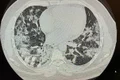

Numărul locuitorilor municipiului Suceava infectaţi cu SARS-CoV-2 a trecut de pragul de 3 la mia de locuitori. Comitetul Judeţean pentru Situaţii de Urgenţă se va întruni miercuri, 28 octombrie, pentru a stabili noi măsuri de prevenire a răspândirii virusului în oraş.

Potrivit specialiştilor de la Direcţia de Sănătate Publică Suceava, gradul de infectare cu SARS-COV-2 în municipiul Suceava era marţi, 27 octombrie, de 3,02 la mia de locuitori.